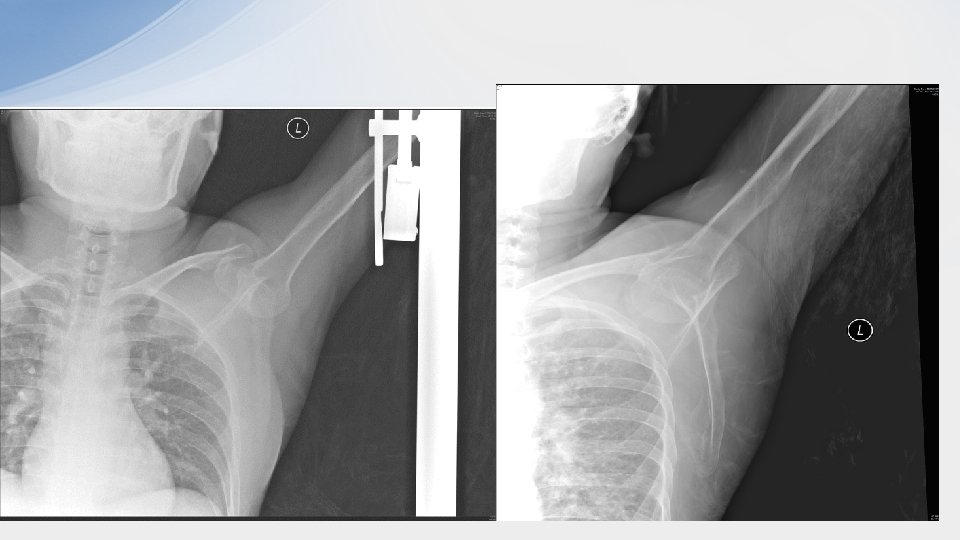

Case 4 • 42/F • S/F while chasing bus • Left shoulder injury

• 1. What are the x ray finding and diagnosis? – X ray AP: • humeral head displaced inferomedically to the glenoid fossa • Humerus in marked abduction – Inferior shoulder dislocation (luxatio erecta)

• 2. what are the 2 possible treatment methods in ED? – Traction and counter traction – 2 -step reduction • Convert the inferior dislocation into an anterior dislocation by pushing the proximal humerus anteriorly while pulling the elbow in a superior position • Adduct the arm • Use any reduction technique for anterior dislocation

• 3. What are the complications of the injury? –Brachial plexus nerve injury esp axillary nerve injury –Axillary artery thrombosis –Rotator cuff injury –Fracture of greater tuberosity of humerus, glenoid rim, acromion or clavicle –Glenolabral tear